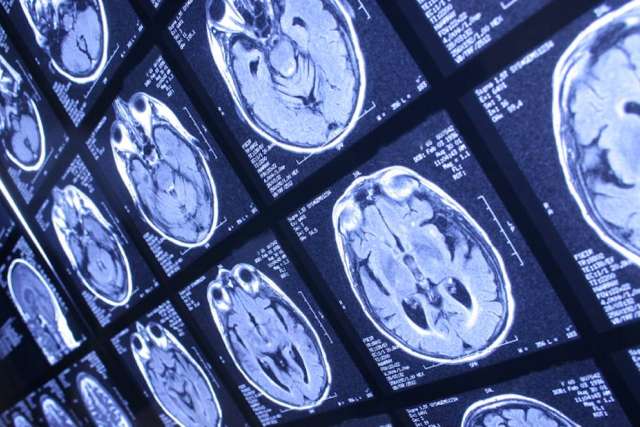

For patients at increased risk of hemorrhagic stroke, a class of cholesterol-lowering drugs known as PCSK9 inhibitors may be a safer choice for cholesterol management than statins, according to a new study by UCLA researchers.

Statins also reduce the risk of the most common type of stroke – ischemic stroke due to plaque buildup in blood vessels. But some studies have suggested they may increase the risk of less-common hemorrhagic strokes – bleeding in the brain due to blood vessel rupture.

They found that statins increased the risk of hemorrhagic stroke very slightly in all patients. The risk was higher in patients taking high doses of statins and in patients who had some baseline injury to the brain from a prior ischemic stroke. And the risk was highest in patients who had already had a prior hemorrhagic stroke.

But in the small subset of patients who had previously suffered a hemorrhagic stroke, taking statins increased their risk of a future brain bleed by about four-fold. Having a prior hemorrhagic stroke already increases the risk of a second one to about 4.7%. Add in statins, and that risk jumps to 16%.

“In contrast, the PCSK9 inhibitors did not show any increase in risk of hemorrhagic stroke,” Saver says.